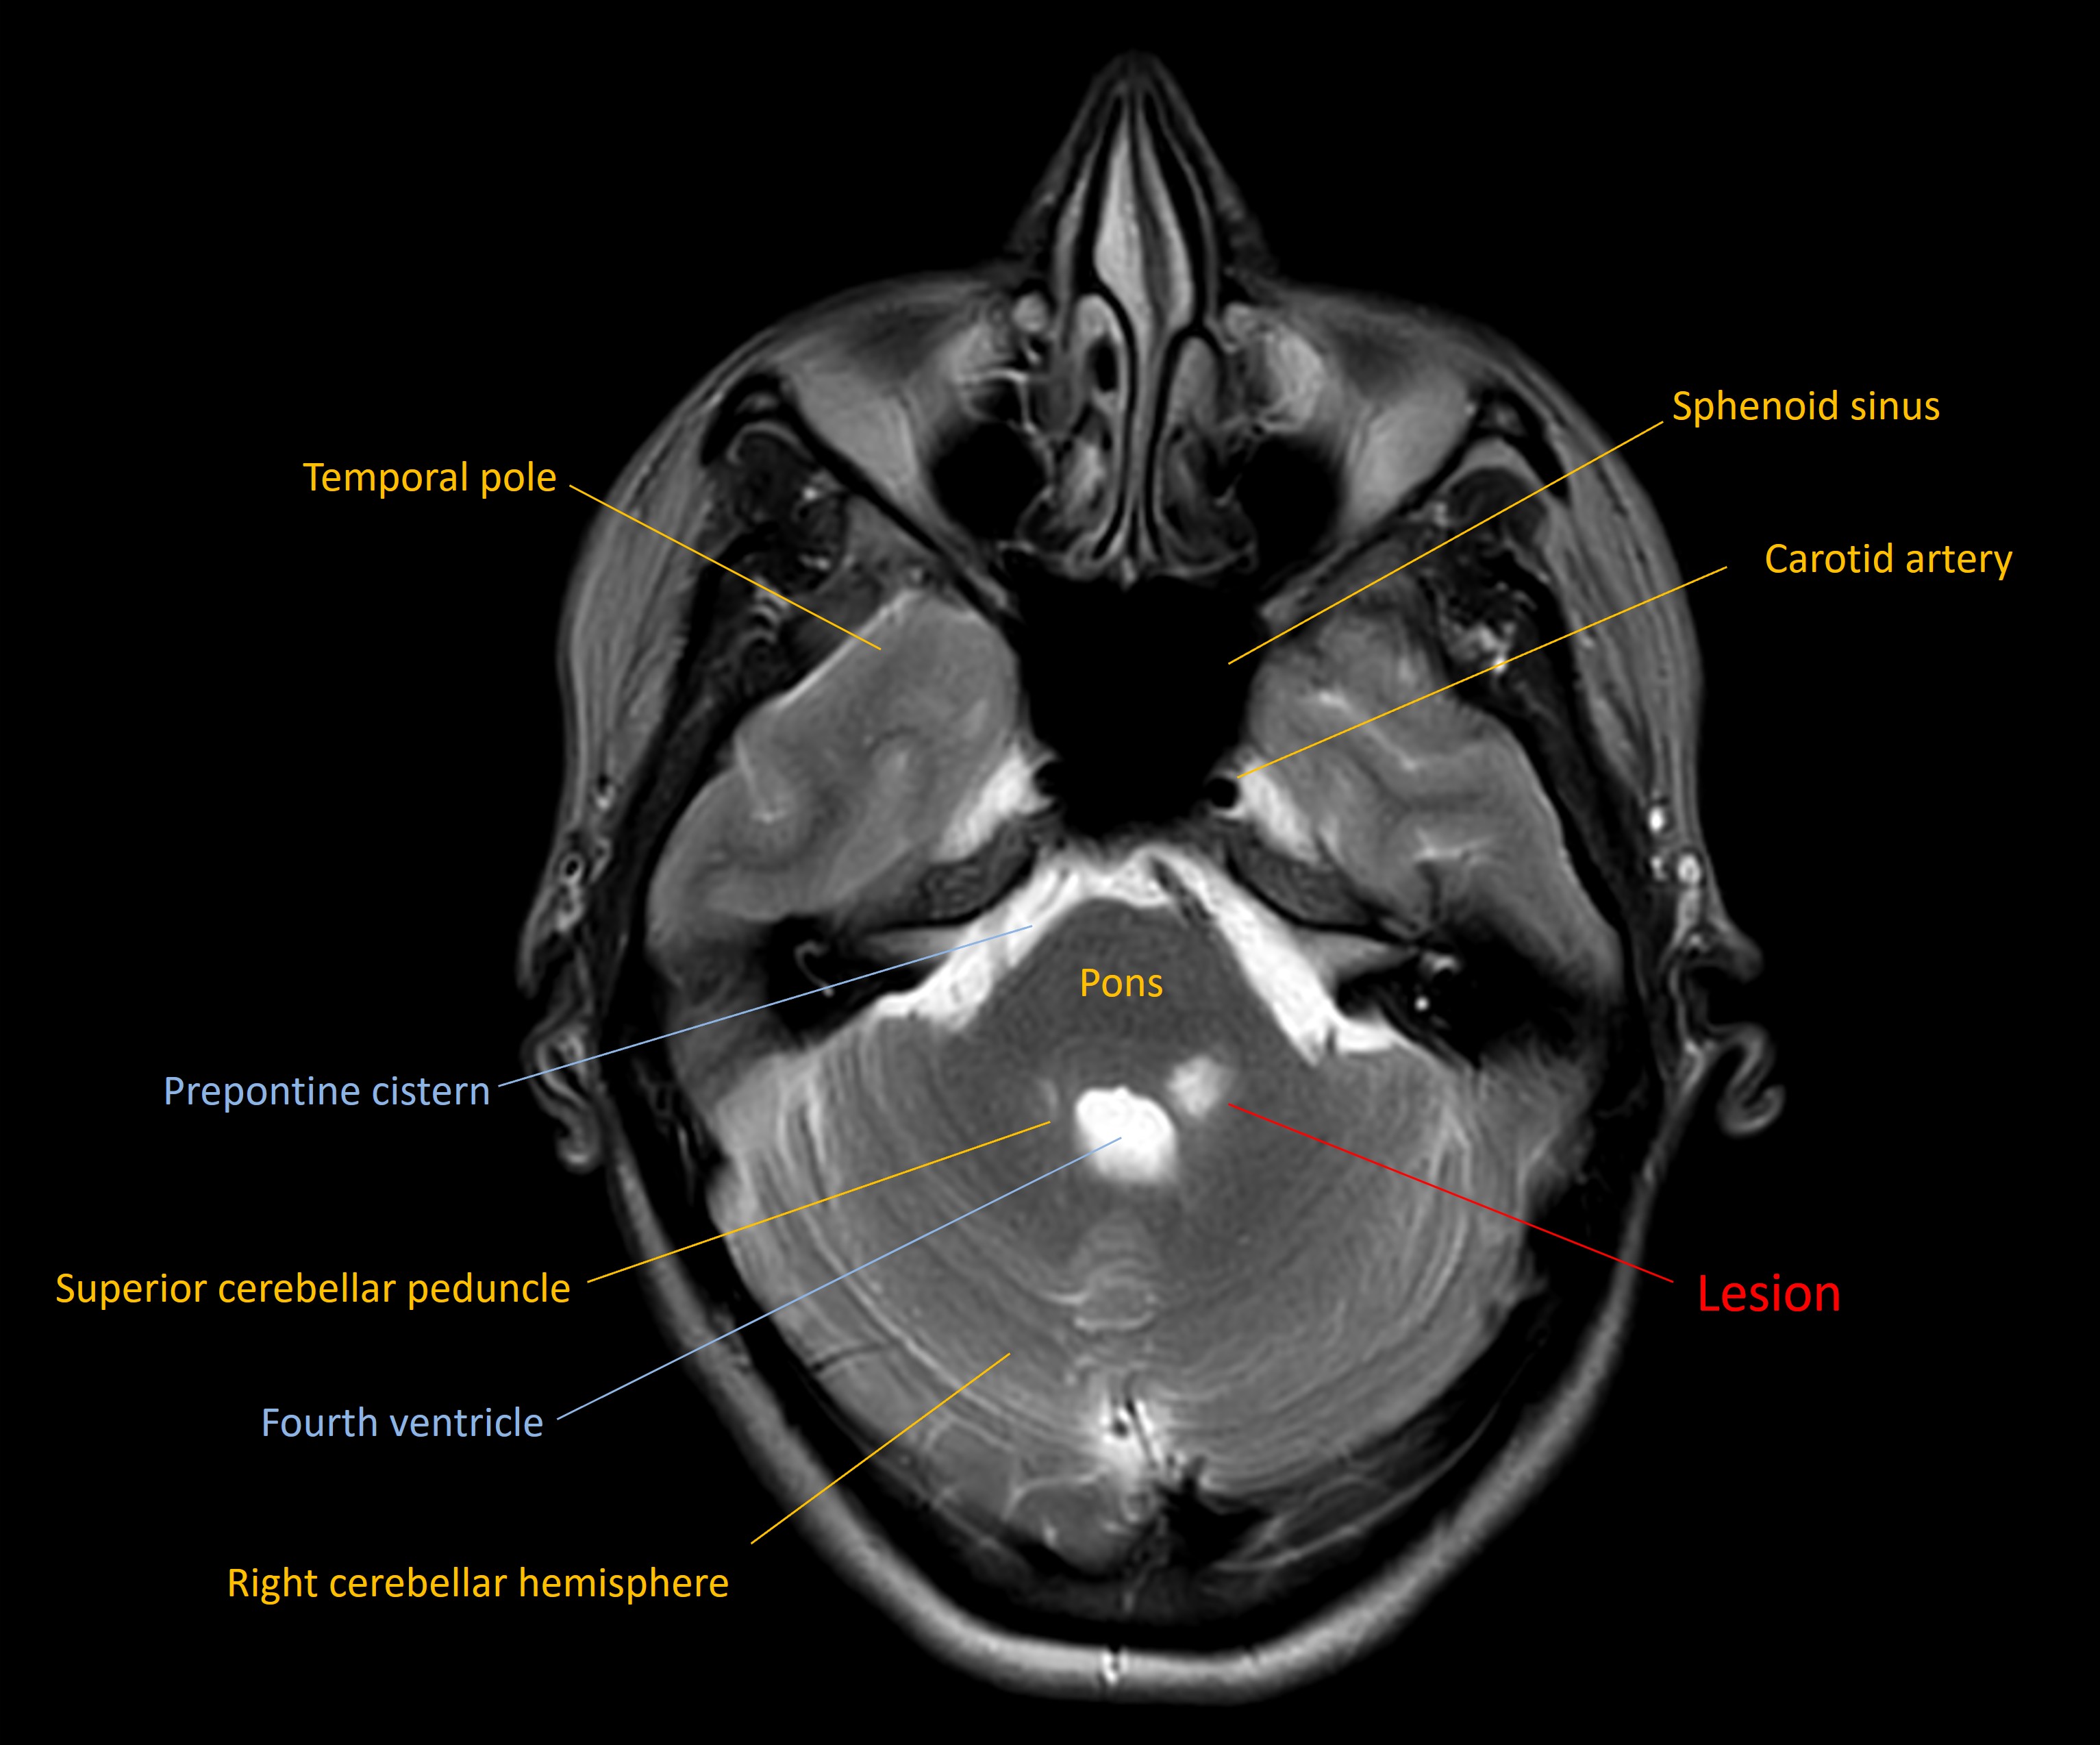

An MRI showed a lesion in the left dorsal upper pons, in the site of the principal trigeminal sensory nucleus - suggestive of demyelination.

This was suggestive of multiple sclerosis (MS), meeting the criteria for dissemination in space . However, insufficient evidence was present to meet the dissemination in time criteria, so the patient underwent another MRI with contrast 3 weeks later. By this time, the pontine lesion was non-enhancing, while there were new, asymptomatic, enhancing lesions present - demonstrating dissemination in time . MS was diagnosed.

Hemifacial numbness due to a demyelinating pontine lesion as the first presentation of MS.